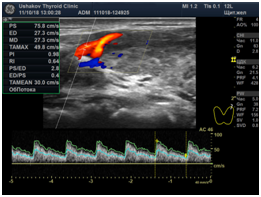

Note that the written Ultrasound Protocol must accompany the images, some of which must be in the "vascular" mode, which are called CDK (color Doppler mapping) and EDK (energy Doppler mapping).

In addition to determining the INTENSITY of blood circulation in the gland, the doctor must determine the SSS (peak systolic blood flow velocity), i.e. the speed of blood flow in the vessels of each lobe. Normally, it is from 20 to 30 cm / s. From 30 to 50 cm / s - a small increase in blood flow, 50-80 cm / s - moderate, more than 80 cm / s - significant. PSSK also allows in figures to estimate a thyroid gland tension.